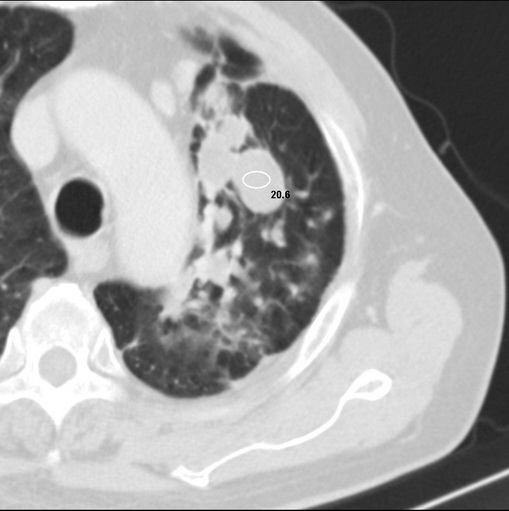

标题: CT25434:胸部CT增强扫描

男性患者 81岁 咳嗽 咳痰 咯血

肿块贴近左肺门,包绕左上肺动脉,形态不规则。肿块增强扫描中度强化。纵膈内主动脉弓左旁间隙、气管隆突前、下间隙见多枚淋巴结影。综上考虑左侧中央型肺癌可能性大。图片没有完整上传,尤其是左肺上叶支气管分支层面没有上传,因此不好判断是叶支气管中断还是段支气管中断。另外,下图红色部分所示是“黏液支气管征”吗?